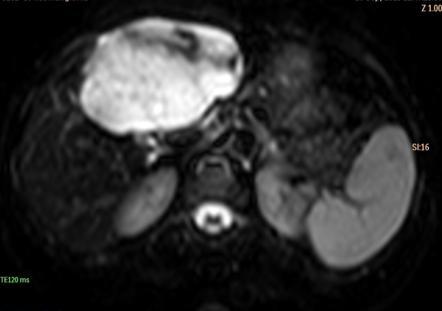

Hemochromatosis on MRI

Increased liver density on CT, decreased signal on MRI

Quick MRI trick to identify a hemangioma

They are one of the only lesions in the abdomen that exhibits the T2 shine phenomenon: Bright on DWI, bright on ADC